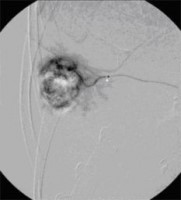

Superselektive transarterielle Chemoembolisation (TACE) mit Sondierung eines tumorversorgenden Gefäßes 2

(Bild 4 von 5)